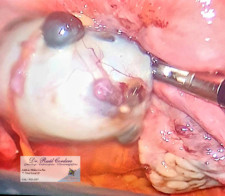

FIBROMA Uterino subseroso por video laparoscopía